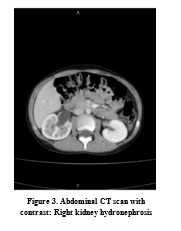

Ultrasonography examination revealed an 81x68 mm cystic lesion behind the pelvis and adjacent to the bladder. Renal ultrasonography reported right renal hydronephrosis.

Computed tomography (CT) revealed a cystic lesion located anterior to the sacrum, between the bladder and rectum. The cyst was dimensioned 108´80´60 mm with a relatively thick wall (4mm) that contained internal densities and fine calcification. Furthermore, right renal hydronephrosis and right ureteral dilatation due to the compressive effect of the lesion were reported. (Figures 1, 2).

After Paraclinical examinations, the patient underwent surgery with a diagnosis of a seminal vesicle cyst. However, the operation revealed that the lesion was a hydatid cyst (Figures 3, 4). The surgeon removed the hydatid cyst, and the lesion was sent for further pathological examination (Figures 5, 6).